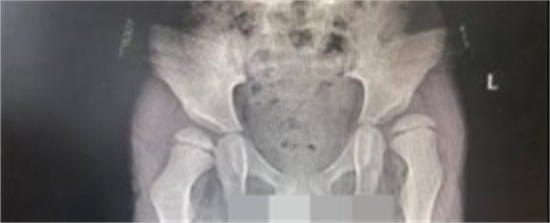

(手术前跳跳的髋关节)

“这类手术都是四级手术,要通过骨盆截骨改善髋臼对股骨头外侧的覆盖,更要通过矫正让偏离的股骨头能够‘回家’,对于主刀医生挑战极高,加上孩子才只有4岁多。”陈文昊说。